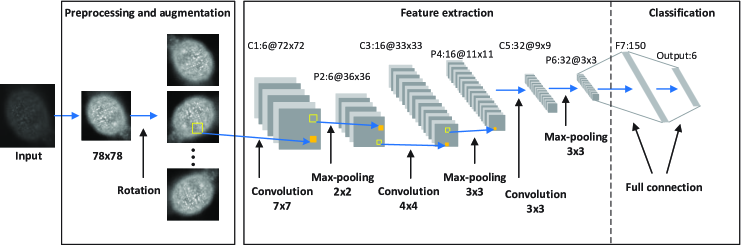

A proper selection of network architecture is crucial to CNNs. Usually, deep CNNs are composed of multiple convolutional layers interlaced with subsampling (pooling) layers, as shown in Fig. 1. Each layer outputs a set of two-dimensional feature maps, each of which represents a specific feature detected from all positions of the input. These feature maps are in turn used as the input of the next layer. Fully-connected layers are usually stacked on the top of the network to conduct classification.

Our deep CNN shares the basic architecture as the classical LeNet-5 (LeCun et al., 1998). Specifically, it contains eight layers. Among them, the first six layers are convolutional layers alternated with pooling layers, and the remaining two are fully-connected layers for classification.

The network architecture of our deep CNN is illustrated in Fig. 1. Specifically, the first layer convolves an input image with each of the six filters of size with a stride of one pixel, and then adds a bias to each of them after convolution. We adopt the hyperbolic tangent function (LeCun et al., 1998) as the activation function. The second layer takes the output of the first layer as input, and applies max-pooling over non-overlapping regions of size for each feature map. The third layer adopts filters of size , and has feature maps. The fourth layer then applies max-pooling over non-overlapping pooling regions of size . The fifth layer employs filters of size and includes feature maps. The sixth layer employs non-overlapping max-pooling to the output maps of the fifth layer. After that, the resulting feature maps of size are cascaded and passed to the first fully-connected layer containing neurons.

When a cell image is fed into the network, the spatial resolution of each feature map decreases as the features are extracted hierarchically from one layer to next. The spatial information of each cell is extracted by the feature maps because of the spatial convolution and pooling operations, which are important to distinct different staining pattern types. The features obtained are invariant to small translation or shift of cell images, because the filter weights of the convolutional layers are uniform for different regions of the input maps and max-pooling is robust to small variations.